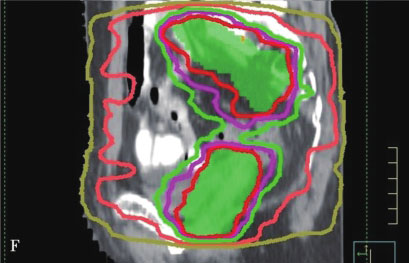

IMRT则是在3DCRT基础上的进一步发展,自1990年代早期IMRT被应用于临床以来,目前已成为一项常规开展的技术。IMRT通过多角度射野设置、多子野分割、滑窗等技术使均匀输出的通量分布变成不均匀分布,明显增加了靶区的剂量适形性,以避免或减少正常组织的照射,最大限度地限制治疗的副作用。IMRT的主要优势是其对凹凸靶区的适形能力,特别是凹面邻近重要器官时尤有优势。据估计,临床治疗的PTV有30%是凹形的靶区,因此可以从IMRT明显获益。另一方面,IMRT治疗方案是在治疗计划系统内通过逆向治疗计划的设计而得到,可以获得较正向计划方法更优的靶区适形性和更窄的侧向半影。通过调节每个射野的通量强度,在肿瘤靶区和正常器官之间形成一个很窄的剂量梯度,通常允许至少95%的PTV接受规定的处方剂量,同时保证周围正常组织的受量在既定的耐受范围之内。图7-2-1为IMRT与3DCRT技术的剂量分布图,其中图A、B、C所示为3DCRT剂量分布,图D、E、F所示为IMRT剂量分布,其中IMRT的剂量靶区适形性明显优于3D-CRT。

图7-2-1 IMRT与3DCRT技术的剂量分布图

A~C.为3DCRT剂量分布;D~F.为IMRT剂量分布